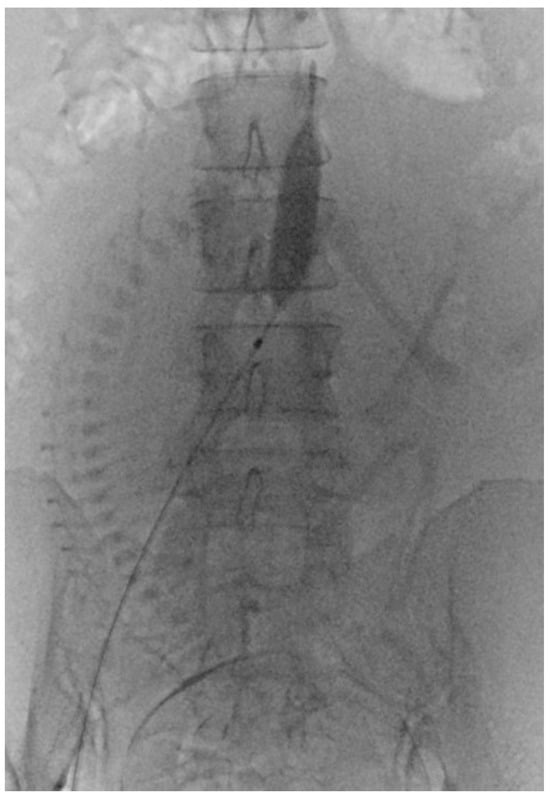

Before PABO, the patients were fully informed of the risks and complications. The procedure involved femoral artery puncture, sheath insertion, and placement of a 7 Fr occlusion balloon catheter. After successfully positioning the catheter, it was securely fastened to the skin. Subsequently, patients were moved from the interventional catheter room to the operating room for a CS. The CS procedure was performed under spinal anesthesia immediately following balloon placement. Following delivery and umbilical cord clamping, the occlusion balloons were inflated in accordance with the obstetrician’s instructions (Figure 2). After delivery, the balloons were deflated prior to skin closure. The radiologist removed the catheters once the patient’s vital signs stabilized, and compression was applied to the puncture sites.

Figure 2.

Prophylactic aortic balloon occlusion during a cesarean section for placenta accreta spectrum and placenta previa.